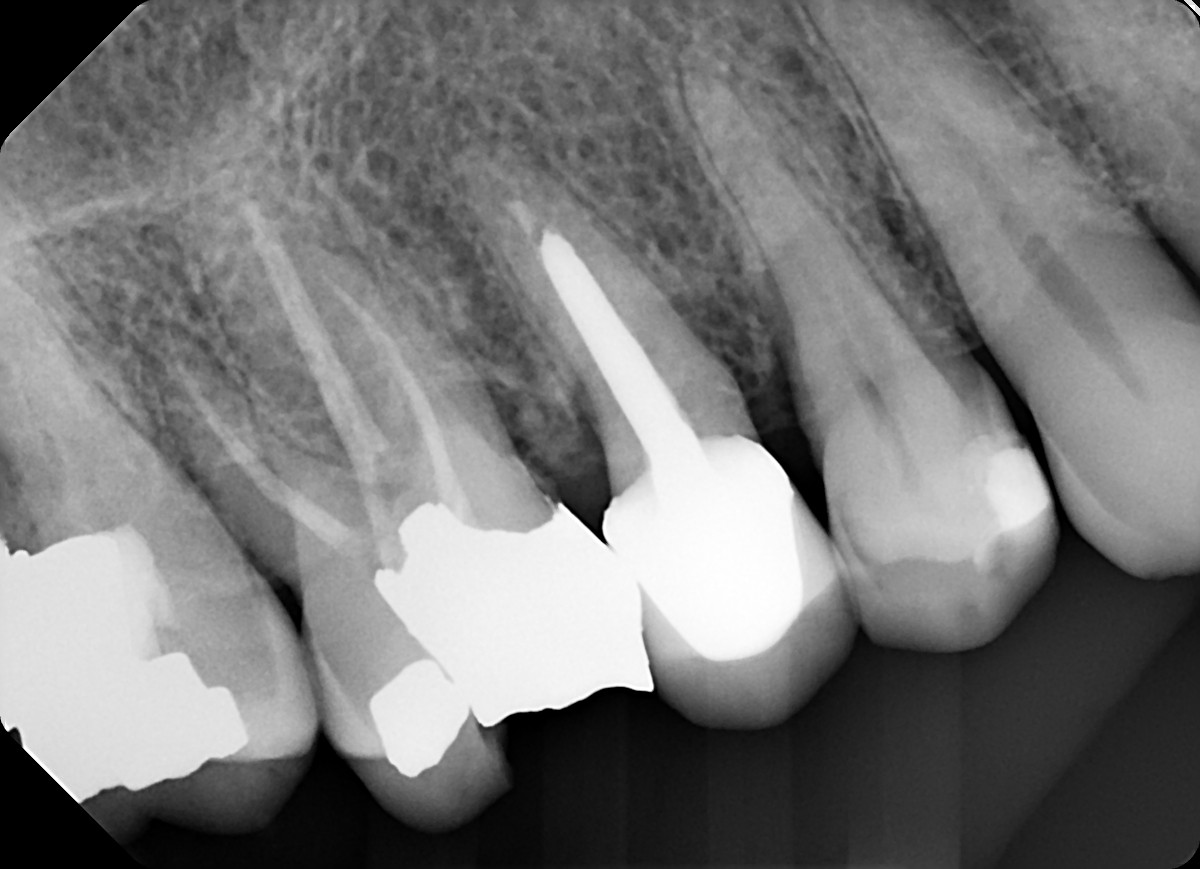

19 / 35

19. On which surface a recurrent caries can be detected?

This is the PA X ray of the question # 18, based on this X ray recurrent X ray for distal tooth # 3.7 can also be selected